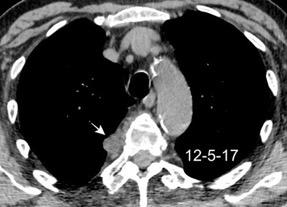

Signos radiológicos TC

Hallifax RJ et al. State-of-the-art: Radiological investigation of pleural disease Respiratory Medicine 2017

Nivel hidroaéreo o burbujas

Forma lenticular o elíptica Ángulos obtusos

> Grasa Extrapleural (60-80%)

Situación no gravitacional (no siempre)

Compresión de estructuras pulmonares

Límite muy bien definido Tabicación

Patrón ecográfico de empiema

Empiema

El derrame paraneumónico se convierte en complicado en 5-10% de los casos

Engrosamiento de la pleura parietal 36/ 59 exudados (61%) 56% de D. paraneumónicos 100% de empiemas Especificidad.. 96%.

Exudado versus trasudado.

Aquino SL, et al. Pleural exudates and transudates: diagnosis with contrast-enhanced CT. Radiology 1994

Signo de la Pleura separada “Split pleural sign”

Capas pleurales de grosor uniforme realzadas por el contraste

Dr. César Pedrosa

No específico de empiema. Indica “exudado”. 68% de pacientes con empiema pleural.

Capas pleurales de grosor uniforme

Realce grasa extrapleural (30%)

> Grasa Extrapleural. (60-80%)

Kraus GJ. Split pleural sign. Radiology 2007